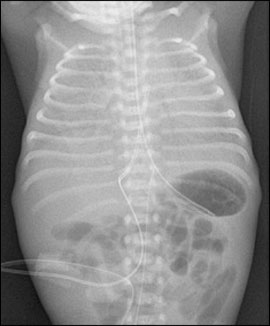

Bilden visar lungröntgen som visar RDS med generellt nedsatt lufthalt.